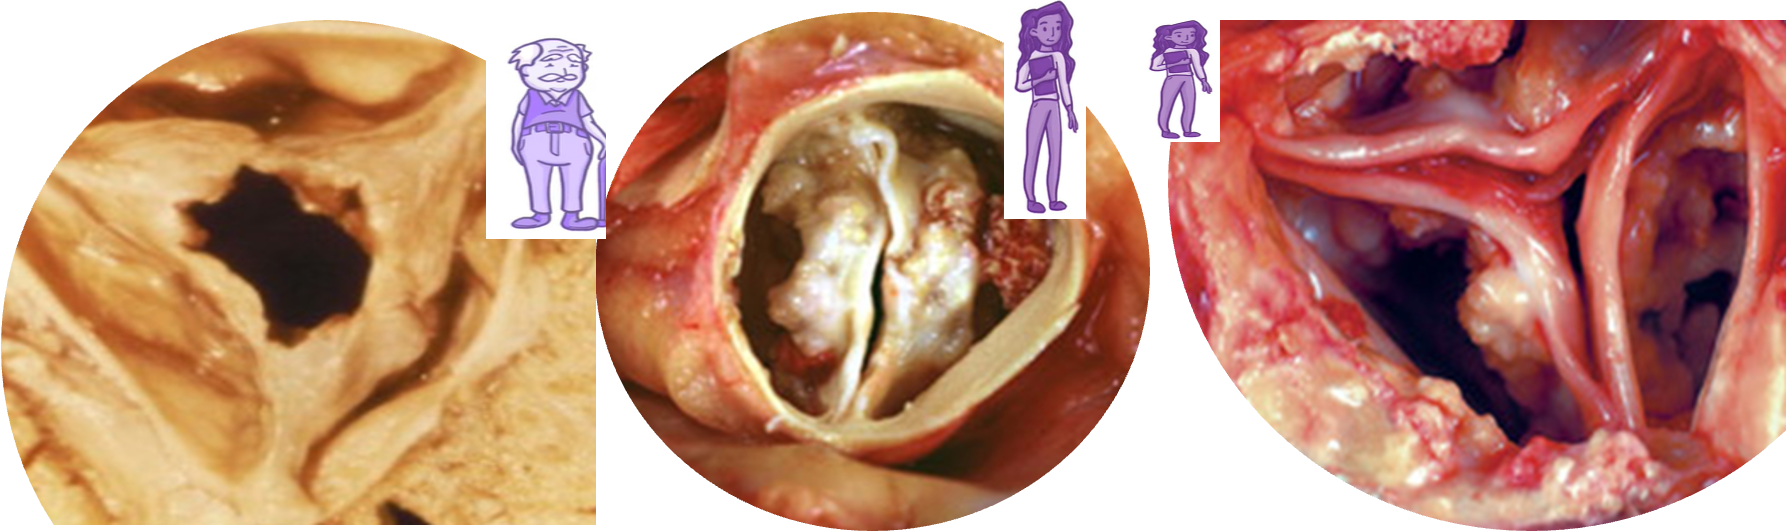

Etiology

- Aortic valve sclerosis: C st. Normal tips. ↑ with age ~ atherosclerosis

- Bicuspid aortic valve (BAV): Fusion leaflets in utero. C: males (3:1). Dystrophic calcification and degeneration. Associated with A coarctation, root dilation & A dissection. Symptoms of AS: earlier than in regular aortic valve calcification.

- Rheumatic fever: C in lower-income countries. Stenosis is caused by commissural fusion. 2nd turbulent flow, calcification of tips.

Epidemiology

- Prevalence: ↑ with age